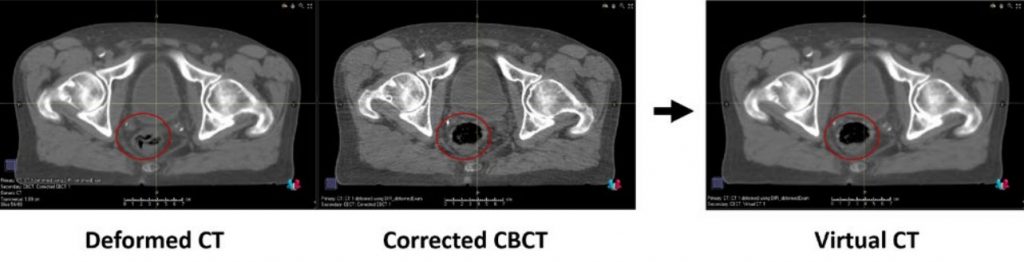

The Corrected CBCT algorithm works in an iterative manner with two main stages; conversion, and correction. These stages are alternated until convergence. The initial stage finds a conversion from the CBCT intensity scale to the planning CT HU intensity scale, and the second finds a correction map that (for each CBCT voxel) removes low frequency artifacts.

The Virtual CT method is a hybrid between a deformed CT and the CBCT correction method. The planning CT is deformed to the CBCT geometry and mismatching low density tissues (air/lung) either in the planning CT or the CBCT, are replaced with values from the corrected CBCT.

Corrected CBCT:

+ No anatomical changes -> No dose errors from incorrect anatomy. Contouring can be safely performed, even easier than on original.

+ Fairly robust to errors in the deformable registration.

– If the original CBCT is of poor quality, some artifacts may remain.

Virtual CT:

+Mostly a deformed CT and will therefore have CT-quality, no/very small additional

dose errors from image quality.

–As it mostly is a deformed CT, accuracy is highly dependent on the deformable

registration

–Deformed CT Contouring should not be done on this image. Use the original CBCT

or (preferably) corrected CBCT.

If the image quality of the CBCT is sufficient, the corrected CBCT is the preferred option.